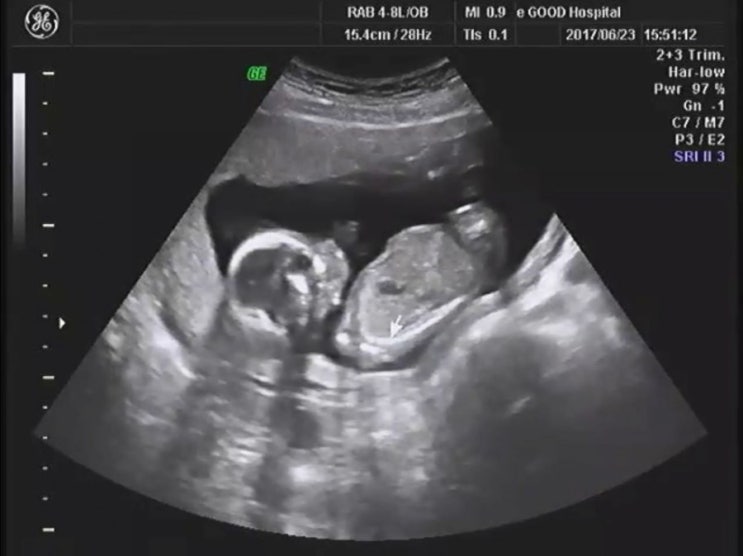

임신16주 전후 증상 / 철분제 힘들어

어느덧 벌써 임신 18주차를 넘어섰다 없어질 듯 완전히 없어지지 않는 입덧탓에 소화불량과 속쓰림으로 힘...